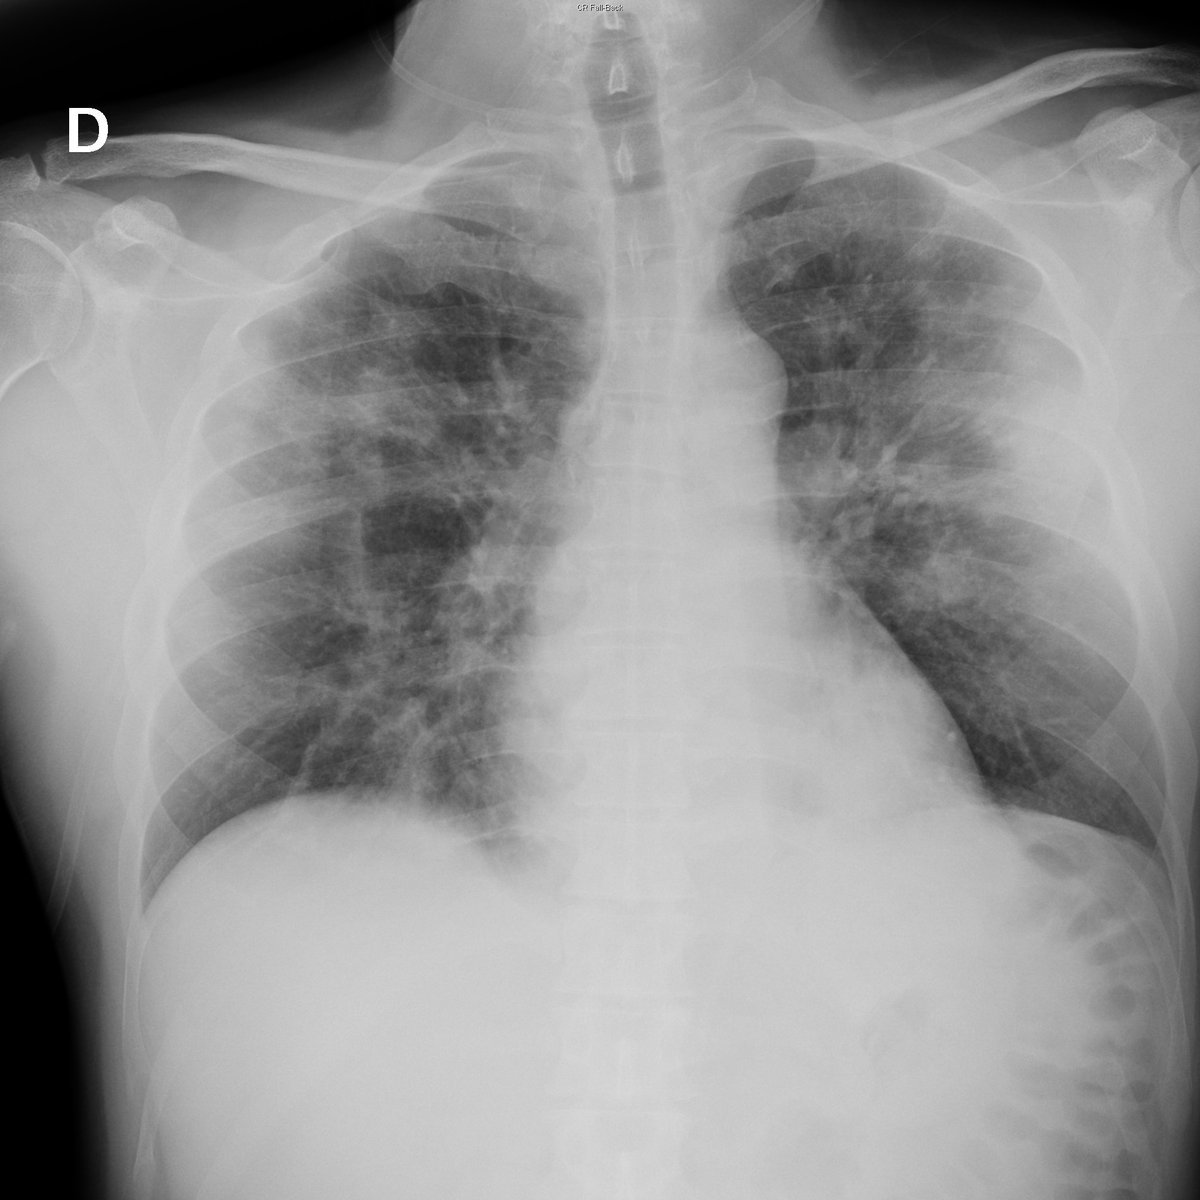

Case 47. 54yo male. Cough and fever. Day 1, 5 (acute respiratory failure), 7 and 9. Small peripheral opacities with progresion toward extensive bilateral consolidation.